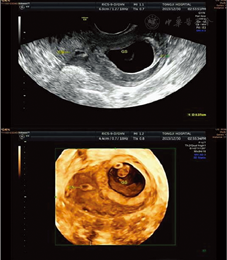

患者于2013年11月15日在本院生殖中心行冻融胚胎移植(FET), 2枚胚胎移植后22 d因阴道出血住院保胎治疗15 d, ET 34 d行B超检查示宫内1个孕囊, 20 mm ×15 mm,胚芽8 mm×3 mm,原始心管搏动好。2013年12月30日三维彩色超声复查示:宫腔左侧角部妊娠[宫腔左侧3.1 cm×2.0 cm孕囊无回声,头臀长(CRL)1.8 cm,可见心管搏动。左侧肌壁厚度0.27 cm, 图1],胚胎存活,宫腔粘连(宫腔右侧可见单层厚度0.2 cm内膜显示,与宫腔不连续)。入院观察, 2014年1月6日三维彩色超声检查示:宫腔左侧角部妊娠(宫腔左侧4.4 cm×3.1 cm孕囊, CRL2.6 cm,左侧肌壁厚度0.34 cm),胚胎存活,宫腔粘连(宫腔右侧可见0.5 cm内膜与宫腔不连续,内可见宽度0.7 cm带状低回声分隔)。患者要求出院观察。2014年2月10日三维彩色超声检查示:左宫角妊娠,左角部肌壁厚0.24 cm,胎盘附着子宫左角部全周及左底部。单活胎(相当于孕14+6周)。入院观察1周,期间向患者交代子宫破裂大出血危及生命风险,患者要求出院继续保胎。孕期门诊常规产检及严密观察。

En示与宫腔不连续内膜; GS示孕囊;绿箭头示左宫角肌层厚度